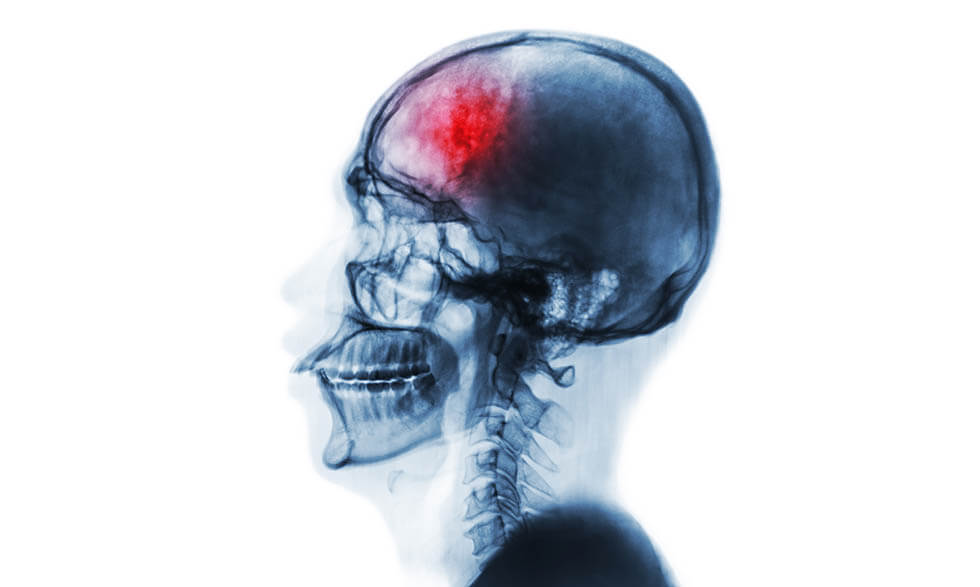

Рентгенография черепа и позвоночника: изображение и диагностика